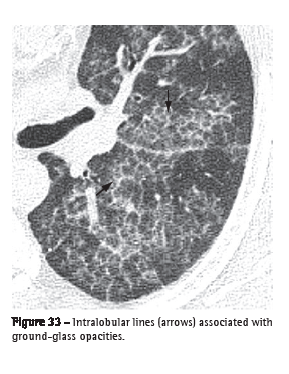

Intralobular lines (linhas intralobulares)

Intralobular lines are seen on HRCT scans as thin linear images within the secondary pulmonary lobule. When numerous, they can have a fine reticular aspect (Figure 33). This finding can be seen in different conditions, especially in cases of fibroses (e.g., usual interstitial pneumonia) and diseases associated with the crazy-paving pattern (e.g., alveolar proteinosis).(3,54)